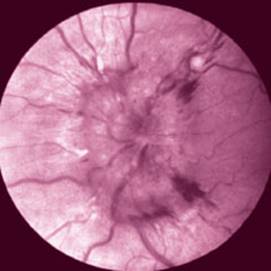

Papilledema is usually a reflection of intracranial hypertension, but it can also be seen in infectious and inflammatory disorders, such as syphilis. The typical findings include a somewhat enlarged, hyperemic optic disc with blurred margins, enlarged veins, and usually hemorrhages (Fig. 11.2). Inexperienced clinicians often have difficulty distinguishing papilledema from other changes of the optic disc.

Fig. 11.2 Acute papilledema (left eye) in a patient with a brain tumor. The optic disc is swollen, with blurred margins and small, linear hemorrhages.